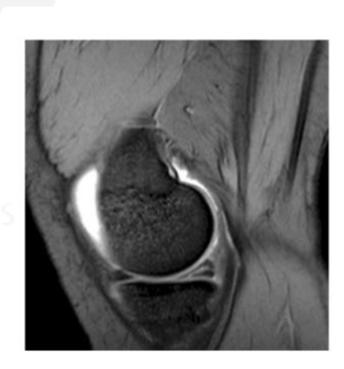

What pathology is seen in this MRI of an 18-year-old male who twisted his knee?

- Posterior horn meniscal tear

- Bucket-handle meniscal tear

What is the significance of the double PCL sign?

- Indicates bucket-handle meniscal tear

What does the white arrow indicate in this image?

- Posterior meniscus horn

What is the diagnosis shown in these images?

- Posterior meniscus horn tear

In an 18-year-old male who twisted his knee during sports, which physical finding is most likely to be found on MRI?